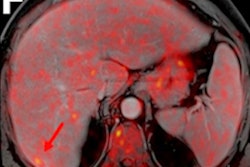

The researchers enrolled 20 prospective patients from January 2018 to June 2019 with chronic degenerative mitral regurgitation. All patients had at least three to four mitral regurgitations and were referred for mitral valve surgery. Each patient underwent simultaneous cardiac F-18 FDG PET and MRI with late gadolinium enhancement imaging on a hybrid PET/MRI system (Biograph-mMR, Siemens Healthineers). Ventricular arrhythmias were categorized as either complex (n = 12) or minor (n = 8).

The researchers detected focal or focal-on-diffuse uptake of F-18 FDG (PET positive) in 17 of 20 patients (85%). The FDG uptake coexisted with areas of late gadolinium enhancement (PET/MRI positive) in 14 patients (70%). All five asymptomatic patients had normal ventricular indices and absence of any surgical indications, and they were PET/MRI positive.

Because the distribution of FDG uptake matched that of late gadolinium enhancement and the PET-positive and late gadolinium enhancement-positive segments tended to be adjacent as well as concordant, which raises the question of "whether there is an inflammatory component of the disease process that is prodromal to the development of left ventricular fibrosis," the authors wrote.